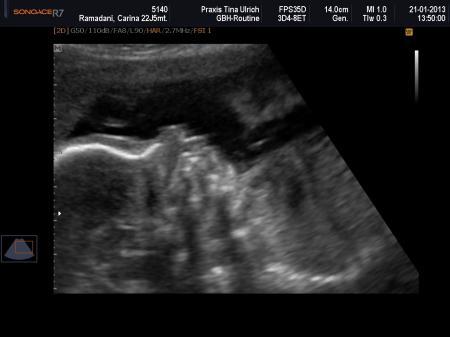

Sooo War ja ausserplanmässig bei meiner FA und was soll ich sagen mit einer strickten Bettruhe bin ich wieder zuhause. Meiner Maus geht es super und ist sehr aktiv hüpfte wie ein Frosch umher. Zunächst wurde festestellt das ich eine Pilzinfektion habe und jetzt mit Zäpfli eine Therapie machen muss dann Wurde noch festgestellt das ich eine tiefe Plazenta habe knapp 1cm vom Mumu entfernt sollte sich aber noch nach oben verlagern wenn das Baby noh mehr wächst. Daher auch meine Blutungen durch die Infektion und die Plazenta. Dann hatte ich gestern tatsächlich Wehen Leider haben die auch was bewirkt, Mumu weich aber noch hinten *zum Glück* und mein Mumu ist etwas leicht verkürzt 30mm deshalb strickte bettruhe Soo dafür ist es jetzt total 100% eine kleine Prinzessin und sie ist topfit und soweit wie man sehen konnte auch gesund